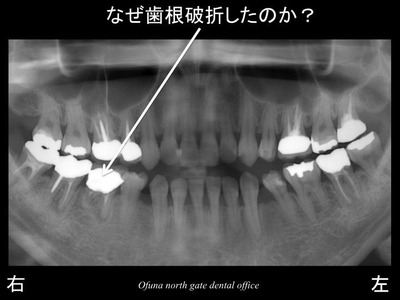

以下が初診時になります。

右下の奥歯が 数年前から腫れて、膿みも出ているため、

他歯科医院を受診したところ

抜歯と言われ、当医院を受診された方です。

診査の結果、下顎右側の奥から3番目の歯は歯根破折 していました。

この歯は治療不可能のため、抜歯と診断しました。

この歯は なぜ歯根破折 したのでしょうか?

当然 1症例目の理由と同じで、神経がないからです。

この患者様の他の歯の状態を見てみましょう!

以下の赤丸は神経がない歯です。

奥歯のほとんどが神経がありません。